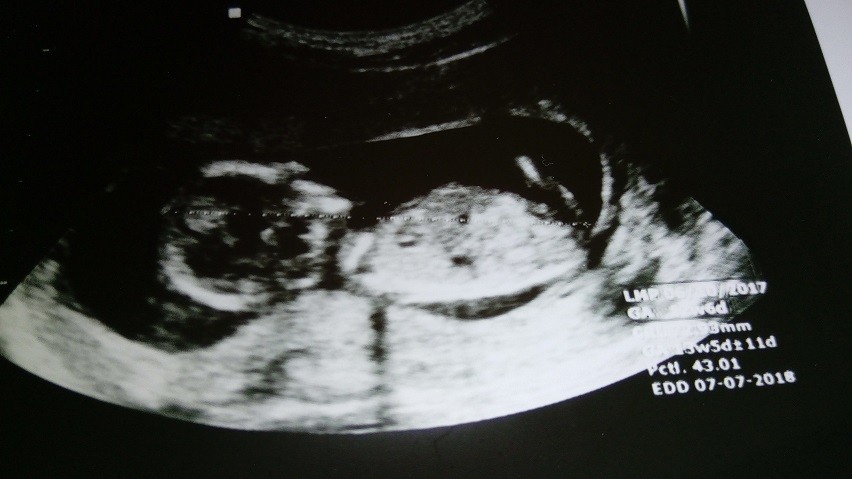

Witam, jestem mamą dwoch synów, teraz jestem w trzeciej ciąży i zastanawiam się co się tam kryje. Czuje, że chłopiec ale cień nadziei na córkę zawsze jest ;) Mam zdjęcie z 12t6d i mam prośbę żebyście zerknęły czy cos z niego da się wyczytać bo ja nic tam nie widze o_O

Załączniki

• IMG_20180105_114956.jpg

Olaaam - witaj a masz jeszcze jakieś foto czy tylko to ?

Ola ja tam nuba niestety nie widzę, raczej nóżka zakryła. A lekarz coś mówił?

Ola ja też nie widzę nuba więc nie będę gdybac. A lekarz co mówił?